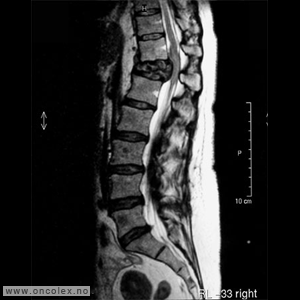

MR er det viktigste diagnostiske hjelpemiddel for å påvise svulst i ryggmargen, ryggmargsnervene og ryggmargshinnene. CT kan også brukes, men har klare begrensninger når det gjelder fremstilling av svulstene. Blant annet kan svulster som ikke tar opp kontrast bli oversett. CT og skjelettrøntgen kan imidlertid være nyttig for å kartlegge grad av skjelettødeleggelse og eventuell instabilitet i ryggsøylen.

Bildeeksempler

En del pasienter med kreft vil oppleve symptomgivende spredningssvulster til ryggradskanalen. Disse svulstene ligger som oftest utenfor ryggmargshinnene som kler ryggmargen (såkalte ekstradurale metastaser), og denne type spredning er vanligst ved bryst-, lunge-, prostata- og nyrekreft. Også benmargskreft (myelomatose) kan føre til påvirkning av ryggmargen, oftest ved at svulsten trykker på ryggmargen, Dette kan skje ved at svulsten selv vokser inn i ryggradskanalen, eller ved sammentrykning eller brudd av en eller flere ryggvirvler som medfører at deler av ryggvirvelen skyves inn i ryggradskanalen.

Malign medullakompresjon (MMK, også kalt truende tverrsnittssyndrom)